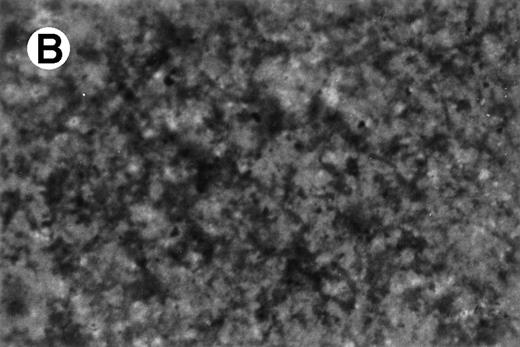

Specific staining showed that UG3 cells cultured with IL-3 were 98% positive for αNB esterase, 13% double-positive for αNB and NAC esterase (Fig 5A), and negative for peroxidase and NAP (data not shown). UG3 cells cultured with GM-CSF showed increased αNB activity and decreased NAC activity (Fig 5B) as compared with UG3 cells maintained in the presence of IL-3. A few of the cells cultured in the presence of GM-CSF were of macrophage-like appearance, having wide and irregular cytoplasm, and grew adherently. In contrast, about 45% of UG3 that were cultured in the presence of M-CSF grew adherently. Nonadherent cells obtained from M-CSF–supplemented culture showed the same morphological characteristics as UG3 cells that had been maintained in the presence of IL-3, but stained 100% positive for αNB and negative for NAC esterase (Fig 5C). Adherent cells obtained from cultures maintained in the presence of M-CSF showed macrophage-like morphology with widely spread cytoplasm containing vacuoles (Fig6A) and also displayed strong positivity for αNB esterase (Fig 6B). In contrast, UG3 cells cultured in the presence of G-CSF featured a slightly irregular cytoplasm, contained granules, and showed increase of NAC esterase positivity (Fig 5D). These cells were 4% positive for peroxidase (Fig 7A) and 6% for NAP (Fig7B). Some UG3 cells maintained in the presence of G-CSF had a segmented nucleus (Fig 7A).

Double staining for α-naphthyl butyrate esterase and naphthol AS-D chloracetate esterase of UG3 cells cultured with IL-3 (5 ng/mL; A), GM-CSF (1 ng/mL; B), M-CSF (100 ng/mL; C), and G-CSF (10 ng/mL; D) for 2 weeks. Original magnification, 200-fold. Histochemical analyses were performed using samples taken from four independent cell cultures.

CD68 expression was determined by immunohistochemistry of UG3 cells cultured with IL-3 (5 ng/mL; A), GM-CSF (1 ng/mL; B), or M-CSF (100 ng/mL; C) for 2 weeks. Original magnification, 200-fold. Histochemical analysis was performed with samples taken from three independent cultures.